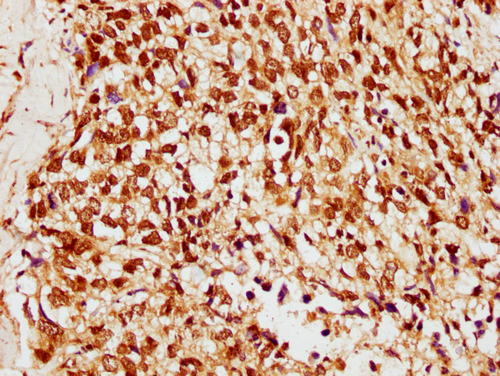

IHC image of CSB-PA010378OA33ncrHU diluted at 1:10 and staining in paraffin-embedded human ovarian cancer performed on a Leica BondTM system. After dewaxing and hydration, antigen retrieval was mediated by high pressure in a citrate buffer (pH 6.0). Section was blocked with 10% normal goat serum 30min at RT. Then primary antibody (1% BSA) was incubated at 4°C overnight. The primary is detected by a biotinylated secondary antibody and visualized using an HRP conjugated SP system.